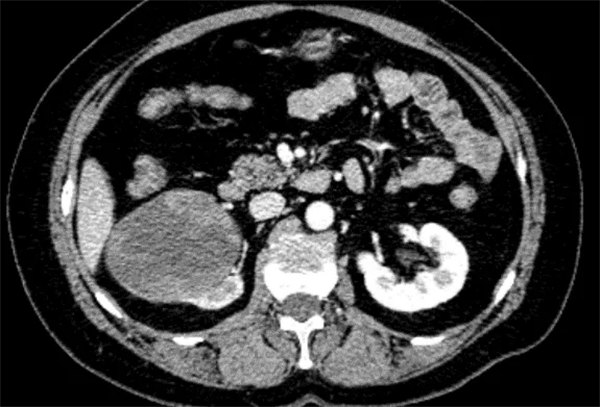

為了進一步治療至我院泌尿外科就診,完善下腹部、盆腔增強掃描+雙腎動脈CTA,經泌尿外科、醫學影像科等多個科室討論后一致診斷為惡性腫瘤。

匯報泌尿病院院長李穎毅,考慮患者腫瘤體積較大、呈膨脹性生長、突向腎竇。若經后腹腔手術,空間有限,且易損傷到腫瘤組織,科室高度重視患者病情,組織圍手術期相關的麻醉手術科、心內科、重癥醫學科、影像科等多個學科的專家進行多學科綜合會診(MDT),確定采用機器人輔助腹腔鏡技術,為患者實施機器人輔助腹腔鏡右腎根治性切除術”。